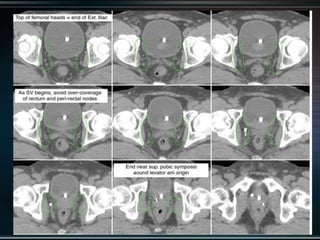

RTOG GU Consensus on pelvic LN CTV volumes:

 Commence contouring the pelvic CTV LN volumes at the L5/ S1

interspace (the level of the distal common iliac and proximal

presacral lymph nodes).

 Place a 7-mm margin around the iliac vessels connecting the

external and internal iliac contours on each slice, carving out

bowel, bladder, and bone.

 Contour presacral lymph nodes from S1 through S3, posterior

border being the anterior sacrum, and anterior border

approximately 10 mm anterior to the anterior sacral bone

carving out bowel, bladder, and bone.

 Stop external iliac CTV lymph node contours at the top of the

femoral heads (bony landmark for the inguinal ligament).

 Stop contours of the obturator CTV lymph nodes at the top of

the symphysis pubis.

RTOG GU Consensuson pelvic LN CTV volumes:  Commence contouring the pelvic CTV LN volumes at the L5/ S1 interspace (the level of the distal common iliac and proximal presacral lymph nodes).  Place a 7-mm margin around the iliac vessels connecting the external and internal iliac contours on each slice, carving out bowel, bladder, and bone.  Contour presacral lymph nodes from S1 through S3, posterior border being the anterior sacrum, and anterior border approximately 10 mm anterior to the anterior sacral bone carving out bowel, bladder, and bone.  Stop external iliac CTV lymph node contours at the top of the femoral heads (bony landmark for the inguinal ligament).  Stop contours of the obturator CTV lymph nodes at the top of the symphysis pubis.